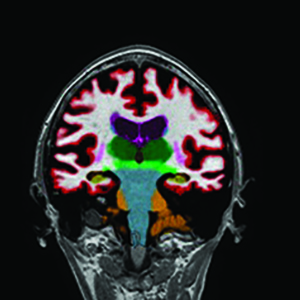

NeuroQuant® is advanced post-processing software designed to help your doctor measure and track changes in brain structure with greater accuracy. This software works along with MRI imaging to create additional views of the brain, assign quantified measurements, and compare to age-matched norms across a database in real-time. This helps your doctor spot early signs of neurological conditions like Alzheimer’s disease, multiple sclerosis, or other conditions affecting the brain. Coupling clear, easy-to-understand visuals with quantitative data, NeuroQuant® gives both you and your doctor valuable insight into your health.

NeuroQuant® works by analyzing images after a brain MRI. The software processes the images and measures the size and shape of key brain regions, including the hippocampus, ventricles and amygdala. Then, it compares your brain’s measurements to a database of healthy individuals your same age and sex. This comparison helps doctors identify whether brain volume is shrinking or changing more than expected, allowing them to monitor for early signs of neurological conditions.

After your MRI is analyzed with NeuroQuant®, your doctor will receive a detailed report showing the size and shape of key areas of your brain. The report includes easy-to-read visuals that compare your brain’s measurements to what’s typical for your age group and sex.

After your brain MRI is completed, NeuroQuant® software analyzes the images to measure the volume in areas of your brain, including the hippocampus, ventricles, and amygdala. It then compares your brain’s structure to a real-time database of healthy individuals your age and sex, helping doctors identify subtle changes that may not be visible with a brain MRI alone.